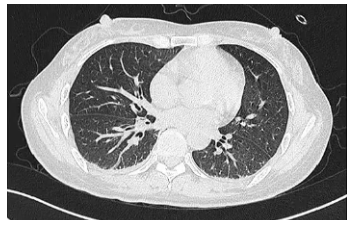

治疗6天后,患者右肺复张,直至转科前,患者肺部未出现任何问题(图5,图6)。于我科有创机械通气30天,未出现呼吸机相关性肺炎。

图6 患者治疗3周后胸部CT

30天后拔管,34天后转科,43天后好转出院,右上肢肌力5-级,右下肢肌力5级。转科当日,平静呼吸,膈肌动度1.35 cm,出院时胸部CT结果正常(图10)。

图10 患者出院时胸部CT